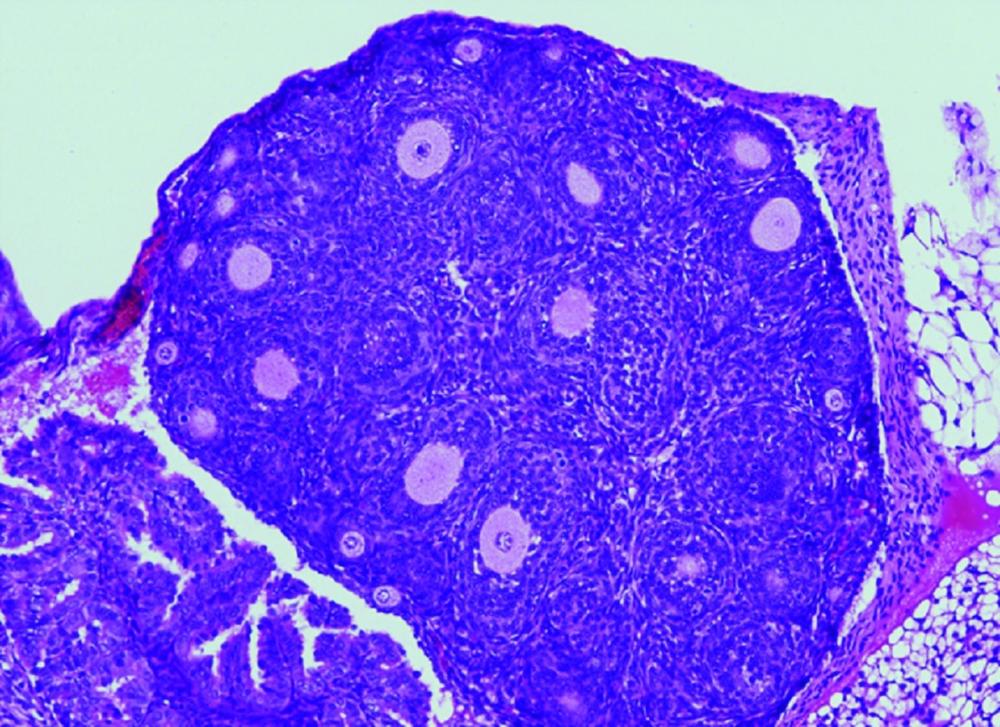

Los tumores de células de la granulosa de adulto (AGCT) son el tipo más común de tumores no epiteliales del ovario. Los AGCT ocurren con mayor frecuencia después de la menopausia y tienen un pronóstico favorable. Las recurrencias agresivas, a menudo fatales, pueden ocurrir hasta en el 50 por ciento de los casos diagnosticados. Como dichos tumores crecen lentamente, pueden reaparecer incluso 30 años después de la extirpación del tumor primario.

«Nuestro grupo ha desarrollado por primera vez un modelo de ratón que alberga en su gen FOXL2 la variante C134W, presente en los tumores humanos, para así poder evaluar in vivo el papel desconocido de FOXL2 en la iniciación y desarrollo tumoral. Para nuestra sorpresa, estos ratones presentan la hipoplasia del párpado observada en el síndrome de blefarofimosis. Curiosamente, las hembras con dicha mutación presentan una fertilidad reducida y lo que es más relevante todas desarrollan AGCT espontáneamente. Es decir, progresan gradualmente de ovarios anormales con células de la granulosa aberrantes a ovarios con hiperplasia estromal y atipia, que finalmente dan lugar a la aparición de tumores ováricos en la totalidad de los animales antes de los 18 meses de edad. Por tanto, este proceso parece estar impulsado únicamente por la presencia de la variante FOXL2», ha explicado Elena Llano, de la Universidad de Salamanca.